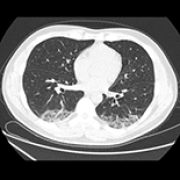

14 Nov 2021 : Clinical Research

Clinical Features and Temporal Lung Radiographic Changes in 25 Patients Recovering from COVID-19 Pneumonia: A Retrospective Case-Control Study

Chao Hu, Jian Ping Zeng, Ke Peng, Hong Xia, Huan Ming Zhang, Zhi Zhong, Ming Yan Jiang

DOI: 10.12659/MSM.933381

Med Sci Monit 2021; 27:e933381

3,640 973 0

3640 973 0